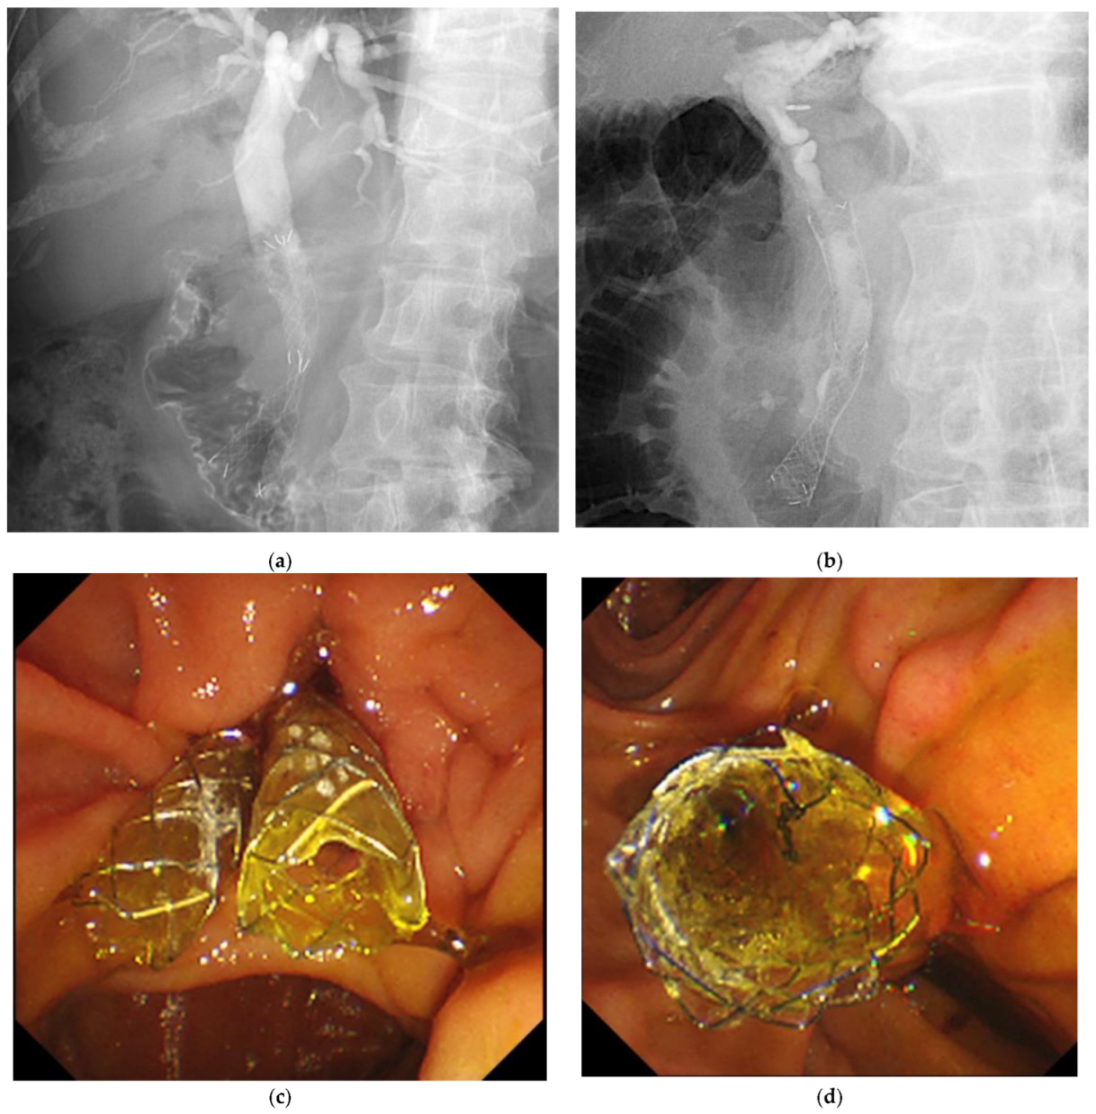

All patients underwent endoscopic biliary drainage via ERCP and were admitted to the hospital on the day of the procedure. Antibiotics and appropriate fluid infusions were administered on the day of the procedure and the following day, respectively. In cases where endoscopic sphincterotomy (EST) had not been performed previously, EST was performed before CSEMS placement. All CSEMS were positioned over the distal bile duct stenosis and released through the papilla. In the DSS group, two slim-diameter CSEMS with a diameter of 6 mm (EGIS biliary stent, SB Kawasumi, Kanagawa, Japan) were deployed (Figure 2a,b), whereas in the Conventional group, a single CSEMS with a wider diameter of 10 mm (BONASTENT, Medico’s HIRATA, Osaka, Japan HIRZO STENTs, Zeon Medical INC., Tokyo, Japan; and Evolution Biliary Controlled-Release Stent, Cook Medical Japan G.K., Tokyo, Japan) was deployed (Figure 2c,d). The fluoroscope used for this procedure was a TJF-Q290V (Olympus, Tokyo, Japan). All cases were performed by a total of three endoscopists with at least 500 cases of ERCP experience as operators.

Figure 2.

Procedure of deployment of DSS and Conventional groups. In the DSS group, two slim-diameter CSEMS with a diameter of 6 mm were positioned over the distal stenosis of the bile duct and released through the papilla (a,b). In the Conventional group, a single CSEMS with a wide diameter of 10 mm was positioned over the distal stenosis of the bile duct and released through the papilla (c,d).